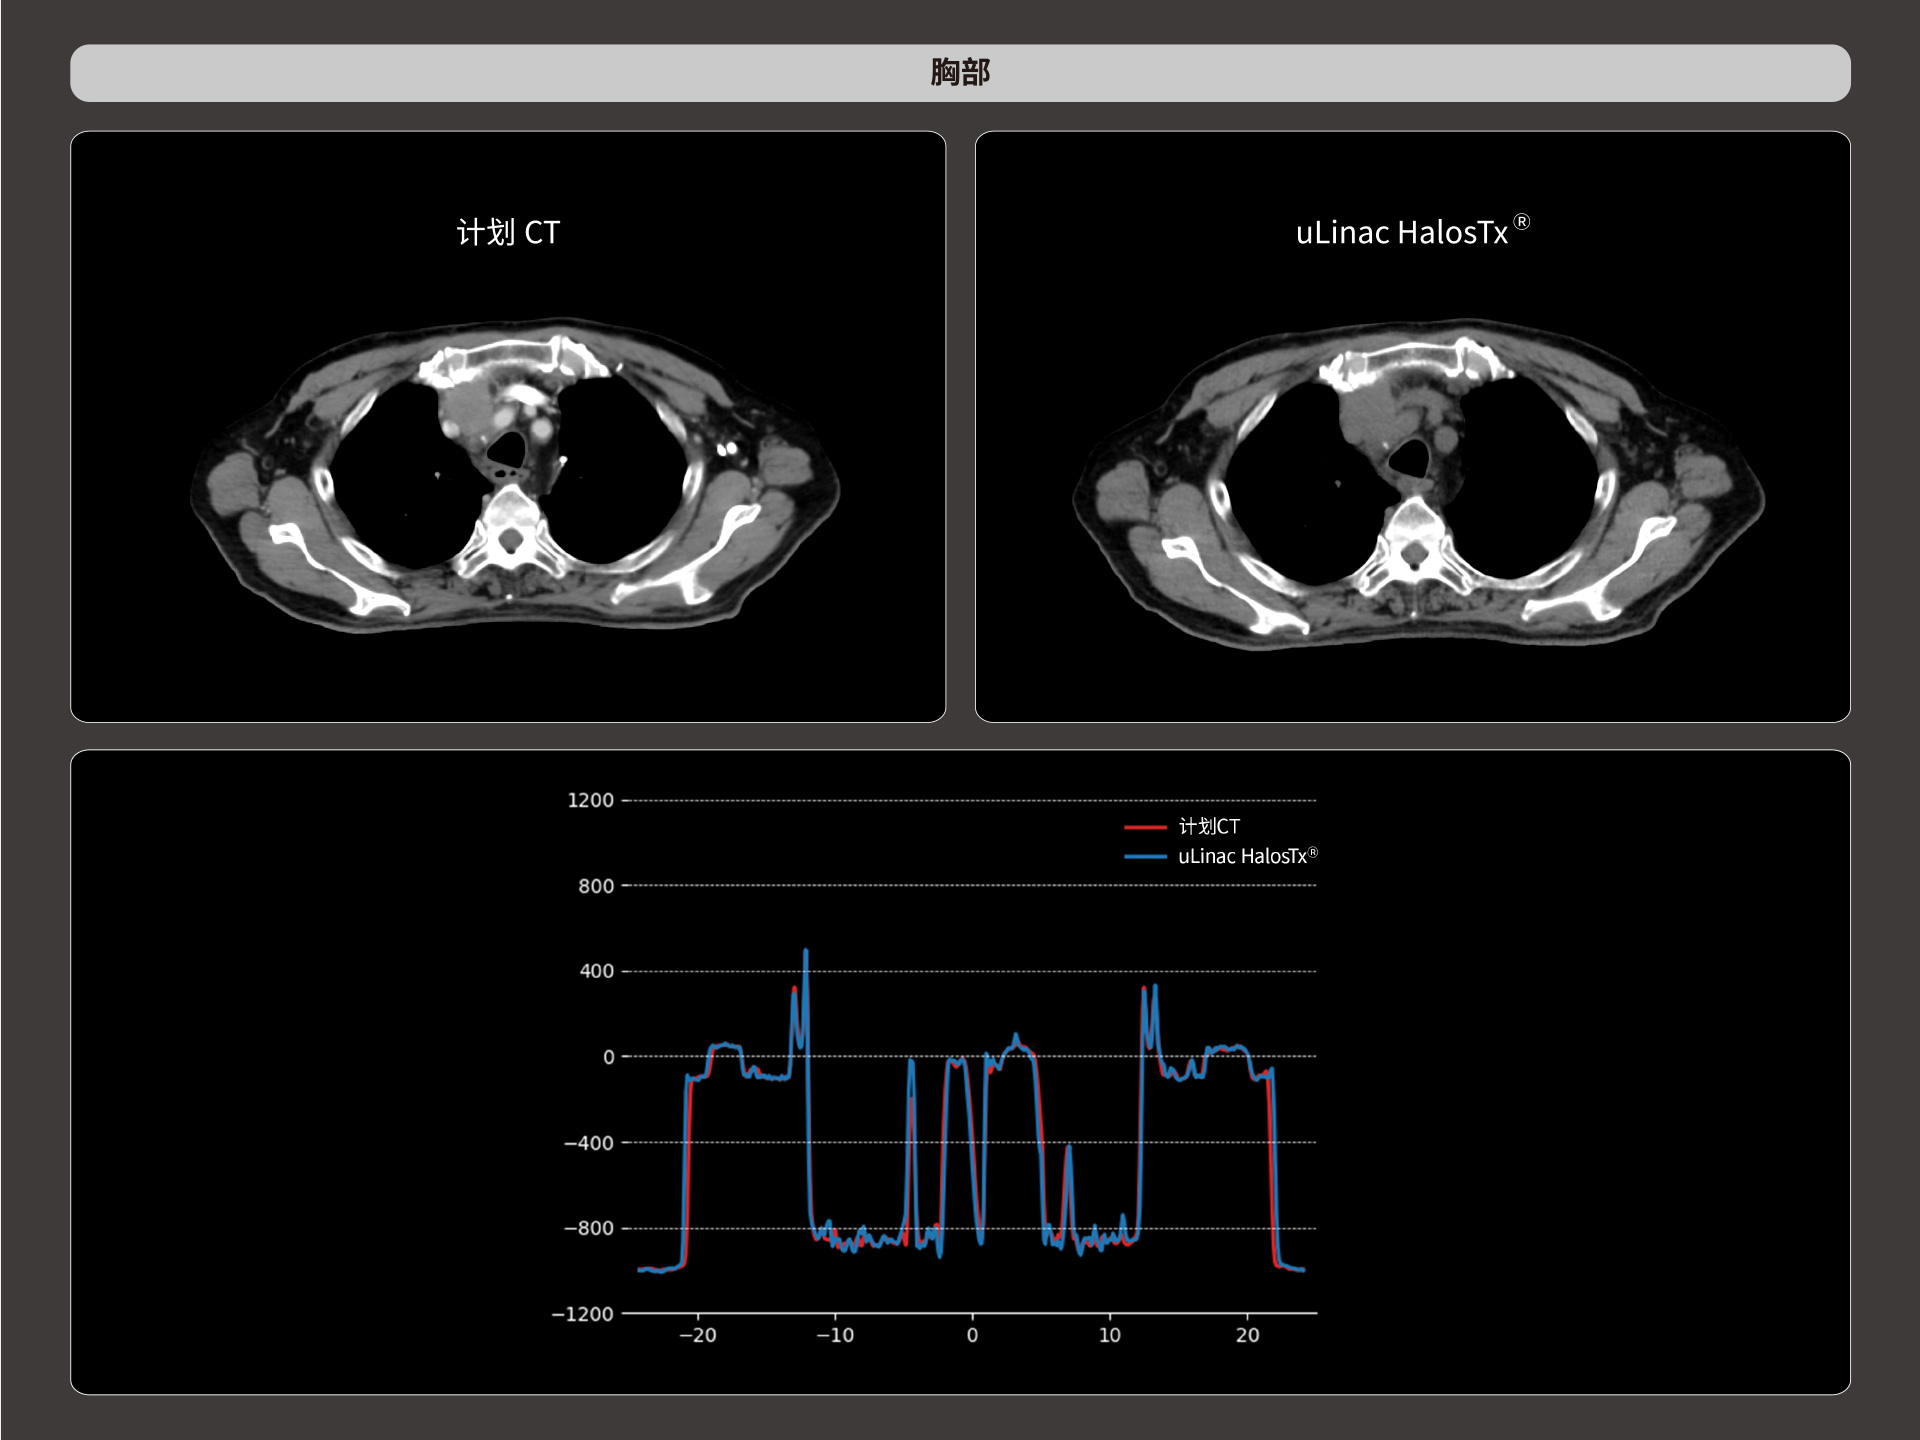

扇形束成像,极低散射,媲美CT-sim的影像品质

3mm @ 0.3% 高软组织对比度,0.55mm薄层扫描,精确鉴别肿瘤靶区边界

HU金标准

精准CT值,完美满足勾画、剂量计算要求

从数据源头提升图像质量,高清呈现细微变化,全面精进机载影像实力

提供传统 的CT 模拟机所一致的HU值精度(±10HU)